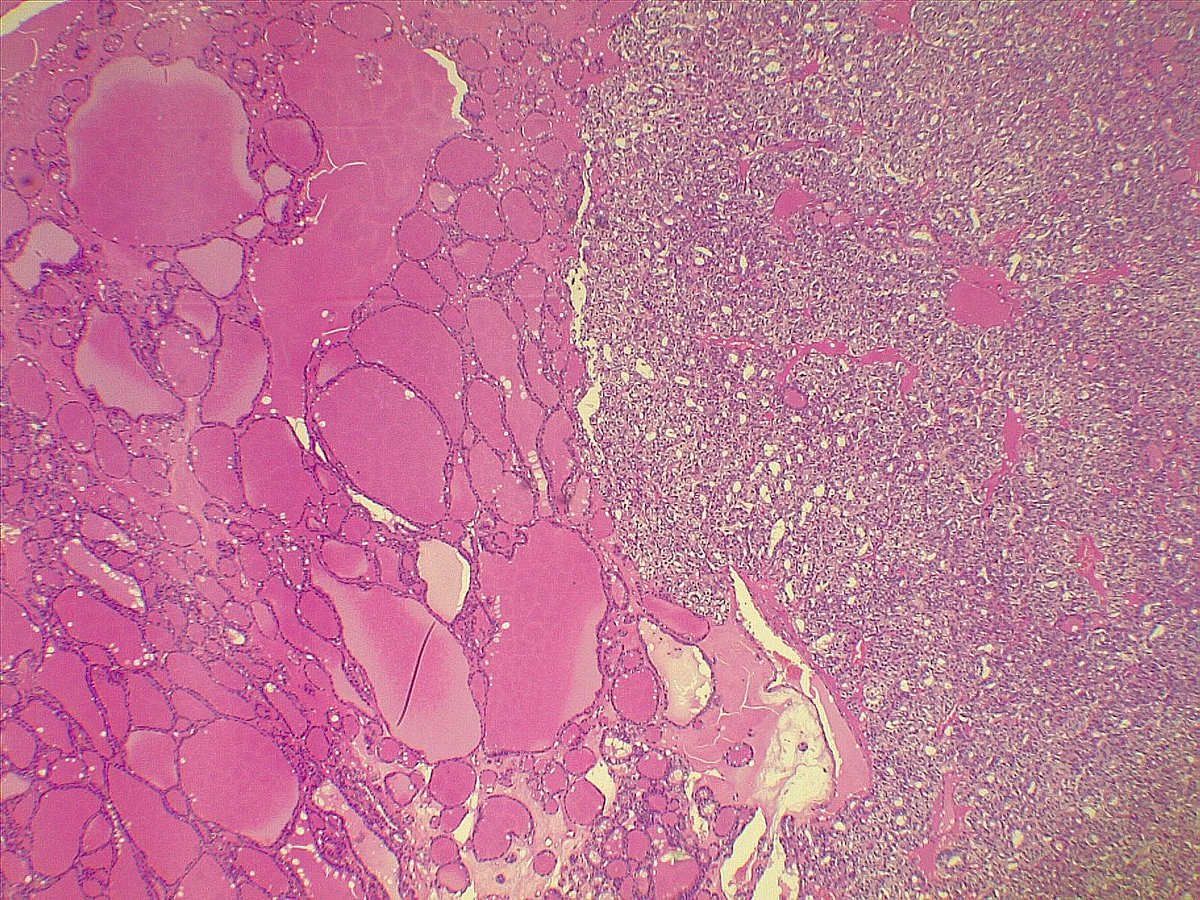

What’s the diagnosis of this spindle cell lesion of breast? 🪡🔬 Poll in the comments 👇 Answer reveal on Monday! 🙌 #PathX #PathTwitter #breastpath